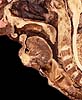

Faringe

Esófago